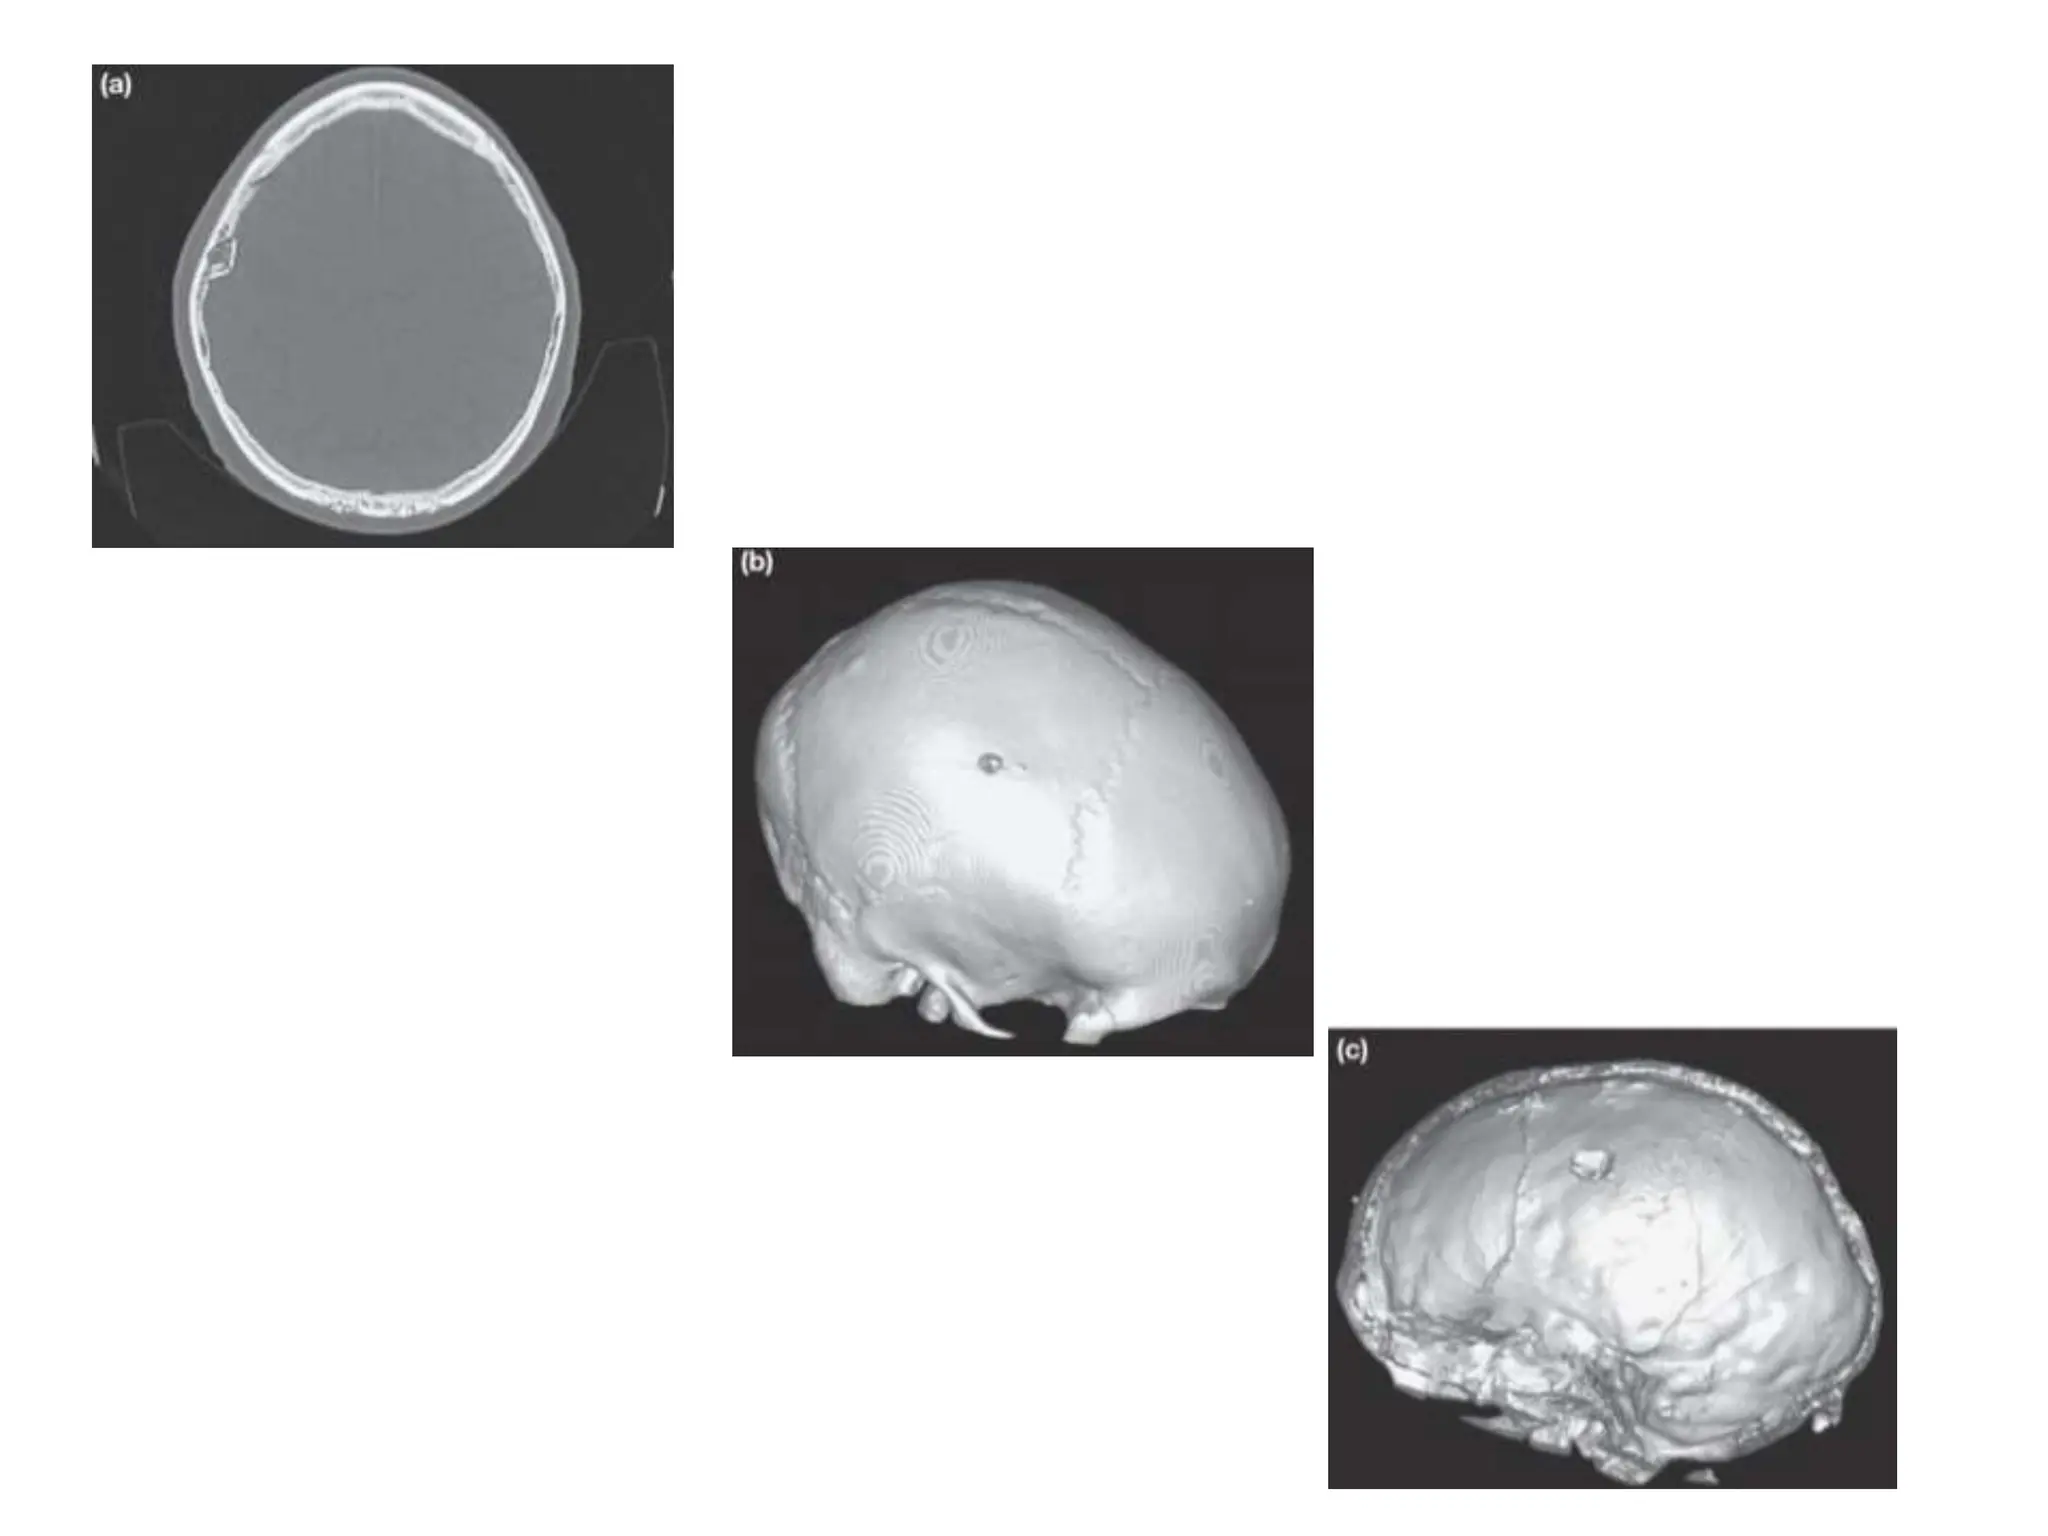

SURGICAL PATHOLOGY Fractures: skullvault • Closed linear fractures of the skull vault are managed conservatively. • Open or comminuted fractures should be considered, debridement and prophylactic antibiotic therapy. • Depressed skull fractures involve inward displacement of a bone fragment by at least the thickness of the skull.

Fractures: skull vault

• Closed linear fractures of the skull vault are

• Open or comminuted fractures should be

• Depressed skull fractures involve inward

displacement of a bone fragment by at least the

thickness of the skull.